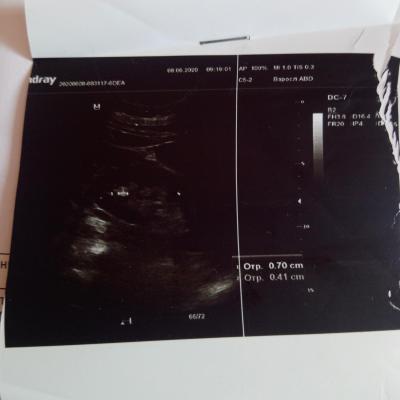

Здравствуйте! Учитывая наличие в моче уратов, можно предпологать , что и конкремент уратный, но необязательно. Целесообразно сделать МСКТ с контрастом - почек и мочеточников ,с 3х мерной реконструкцией. По плотности конкремента можно будет с большей вероятностью предполагать его состав. При конкрементах из солей мочевой кислоты бычно применяют цитратные смеси. При подозрении. по плотности оксалатного характера конкремента, можно рекомендовать комплекс Оксалит. Обсудите эти нюансы с Вашим врачом. Удачи!